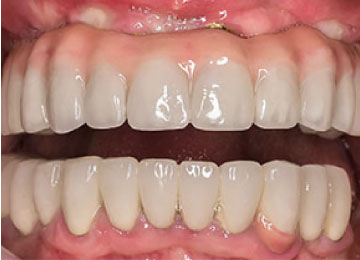

Имплантация зубов: фото «До» и «После»

All-on-4

All-on-6